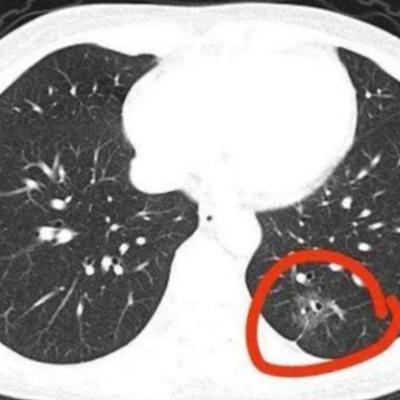

肺部有结节的人,身上基本有这4个表现,千万注意 感冒咳了两周还没好,大多数人的

曾老师杂谈:肺部有结节的人,身上基本有这